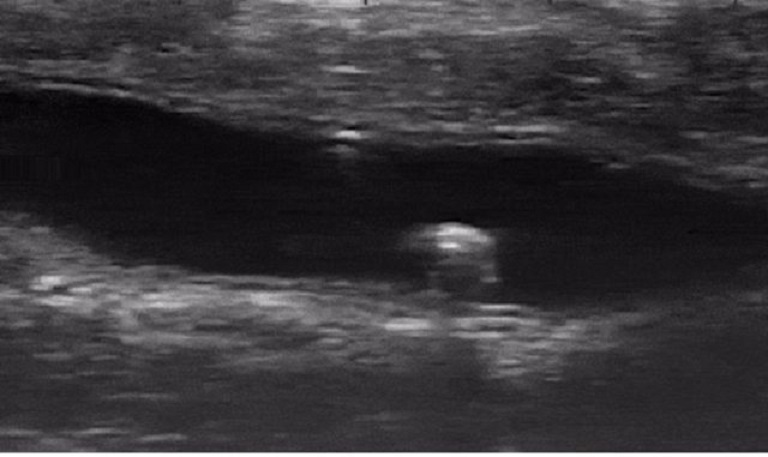

Con robot nhỏ tới mức không thể mang theo pin. Thay vào đó, nó được cấp nguồn và điều khiển từ bên ngoài nhờ từ trường. Nhờ hình ảnh siêu âm, nhóm nghiên cứu có thể theo dõi chuyển động của nó từ bên ngoài ruột kết.